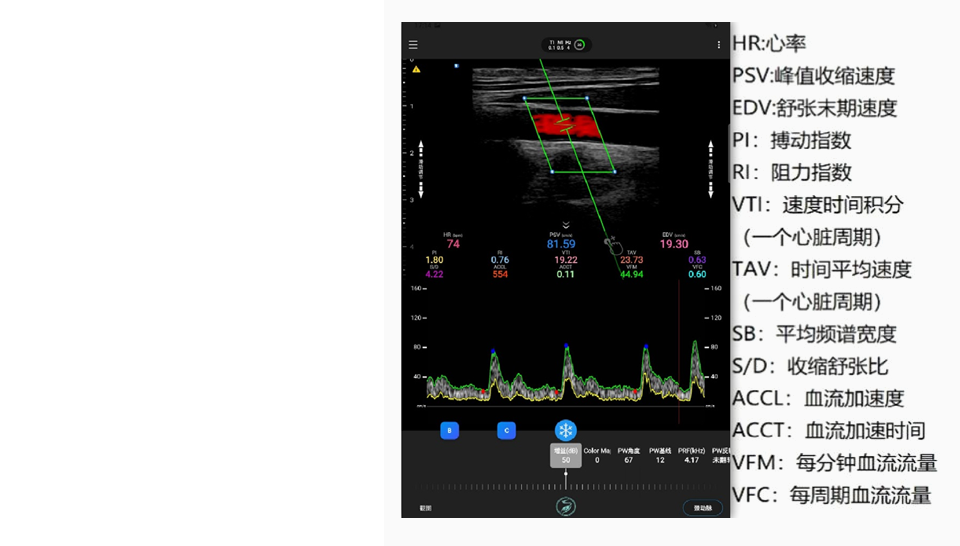

心血管壁垒技术-心血指标自动量化与评估AI技术

心血指标自动量化与评估AI技术,可以准确快速的对13组心血临床指标,进行实时自动量化,并获得13组参数的均值,波动评估值等共计34个评估参数,在大量病例的学习辅助下,有效摒弃的传统人工测量导致的人工引入误差与经验依赖,可快速并全面的评价心血管疾病的存在与严重程度,为心血管慢病的筛查与管理提供重要的辅助量化支持。这将有效缓解对超声医师的技能与经验依赖。